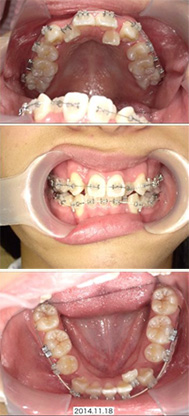

装置をつけて歯を動かす成人矯正永久歯が生え揃ったら、歯並びや咬み合わせが永続的に美しく健康に保てるよう、1本1本の歯を適切な位置に動かしていく治療に入ります。この段階から治療を始める場合、すでに顎の骨が完成しているので、歯並びを整えるために必要なスペースが足りていないことがあります。 |

顎の成長が終了してから抜歯を行い、スペースを確保してそこにゆっくりと歯を移動させていきます。

歯並びも咬み合わせも整い、無事に矯正装置を外すことができました。